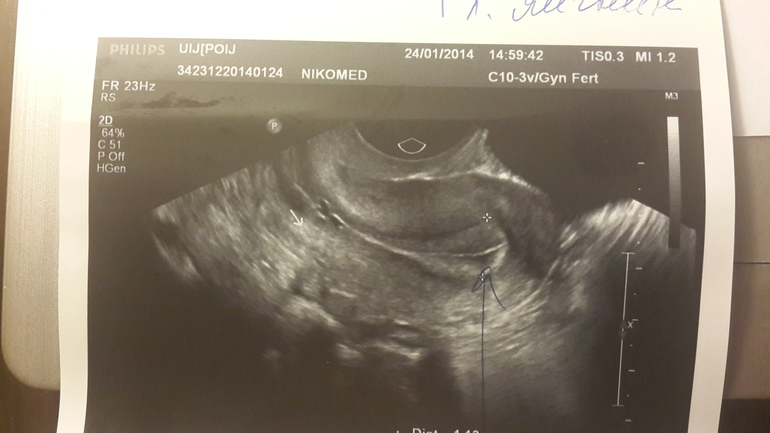

Девчата, кому ставили такой диагноз по узи... откликнитесь! Мне очень нужны фото ваши с узи с маткой! Сегодня на 23 дц увидели эхрнегативное включение 3мм, по передней стенке матки! Никогда я подобного не видела! Всегда все было хорошо! В начале цикла такого не наблюдали! Прошу покидайте фото кому не сложно! Буду очень благодарна вам! И как лечились и беременели! фото под катом

Оба фото с сегодняшнего узи! На первом толком ничего не видно! только хороший эндик.

А вот на втором, датчик иначе доктор повернула, видно образование!

Я отредактировала пост... фото добавила! гляньте! У вас подобное было?

ну я особо по фото узи не понимаю, но у меня тоже маленькая темная точка была выделена...на какой ДЦ вы делали узи?